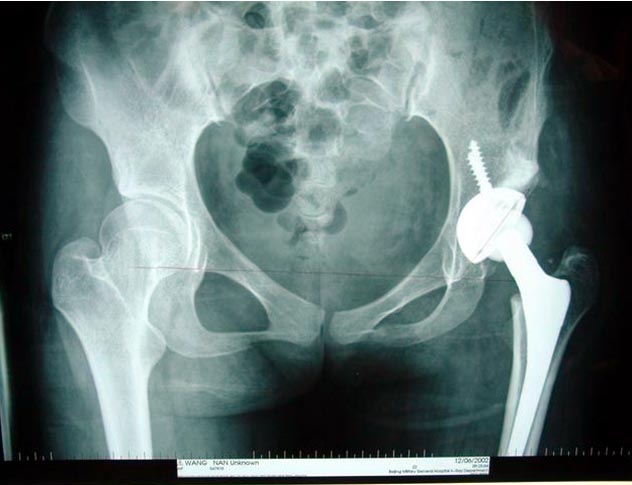

病例二

患者为髋臼嗜酸性肉芽肿,髋臼有骨破坏,患者有疼痛症状。刮除病灶后,采用生物固定全髋关节置换术。

术后4年复查,病灶没有复发,假体没有松动,关节功能良好。